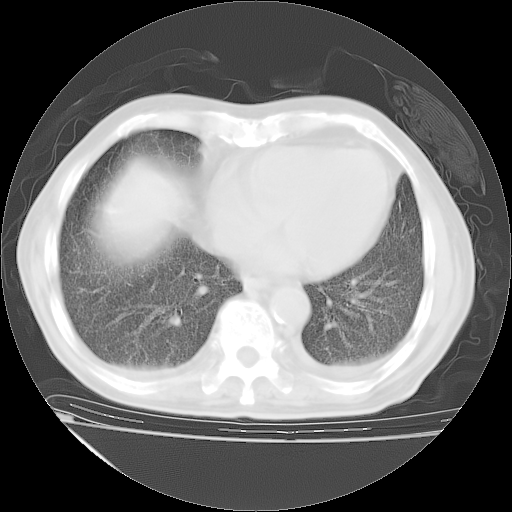

经过24天治疗,岳父的病情基本稳定。生活基本可以自理,可以下床活动。呼吸困难早已消失。体温基本正常。

主要治疗甲强龙80mg×14天,60mg×10天;同时抗结核(异烟肼+利福平+乙胺丁醇)。环磷酰胺0.1 tid 10天。

特别感谢胡教授、高管、桃子版主给出关键的治疗建议。桃版把所有肺部影像和全部临床资料请所在医院呼吸科、感染病科、结核科、临床免疫科专家会诊。临床免疫科专家制定了完整的治疗方案。